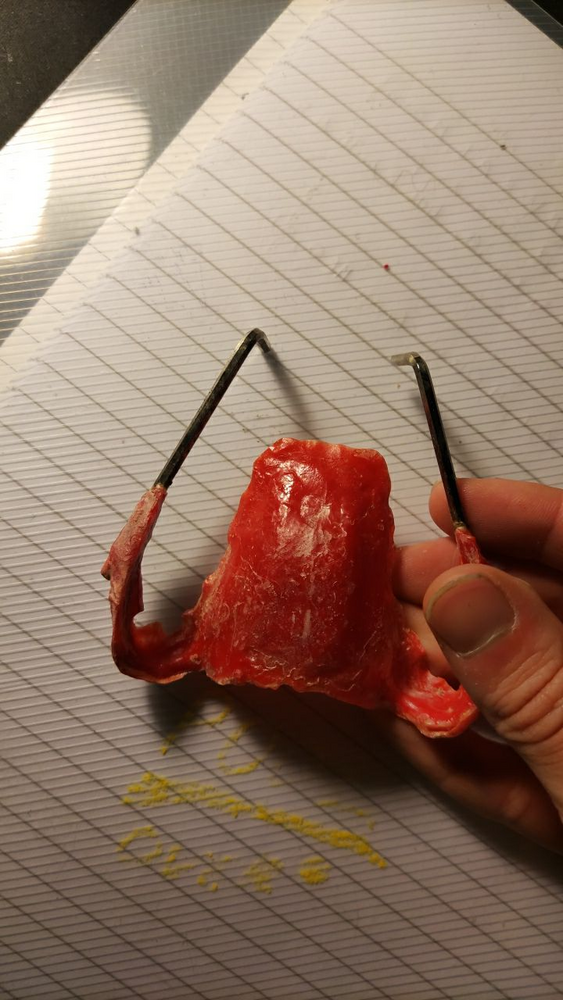

This is MSDO:

MSDO expands the lower jaw (particularly chin). The lower jaw can follow only so much the forced expansion the maxilla is subjected to from the MSE. This, in combination with the MSE can widen the chin, expand the palate, increase the lateral protrusion of the zygos

MSDO expands this much. This is from MSDO only:

This is MSDO:

MSDO expands the lower jaw (particularly chin). The lower jaw can follow only so much the forced expansion the maxilla is subjected to from the MSE. This, in combination with the MSE can widen the chin, expand the palate, increase the lateral protrusion of the zygos

MSDO expands this much. This is from MSDO only: